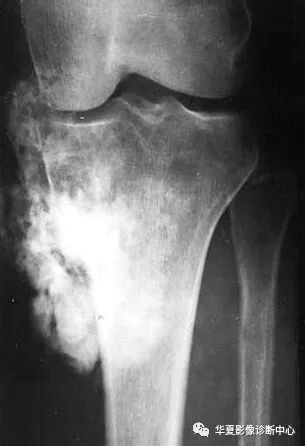

异常骨化有两种表现形式:骨质增生硬化和肿瘤骨。

肿瘤骨:在病灶内或软组织肿块内,是由病理性成骨组织形成的骨质,不能演变为正常的骨质结构。表现为骨内或(和)软组织肿块内云絮状、斑块状、放射状无证正常骨小梁结构的高密度影,其密度可以差异很大。

反应性骨质增生硬化与肿瘤骨最大的不同在于前者在病灶的周围,是由正常的成骨细胞形成的骨质,可演变为正常的骨结构;后者则在病灶内或软组织肿块内,是由病理性成骨组织形成的骨质,不能演变为正常的骨质结构。